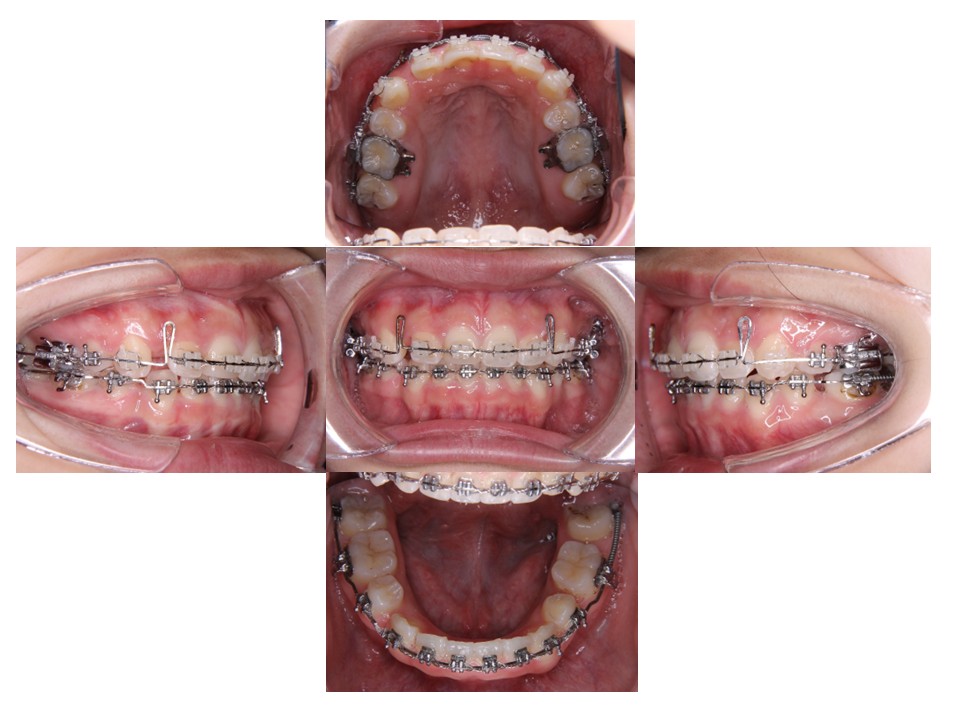

治療結果

上下顎前歯が後退した。

治療期間:2年6ヶ月